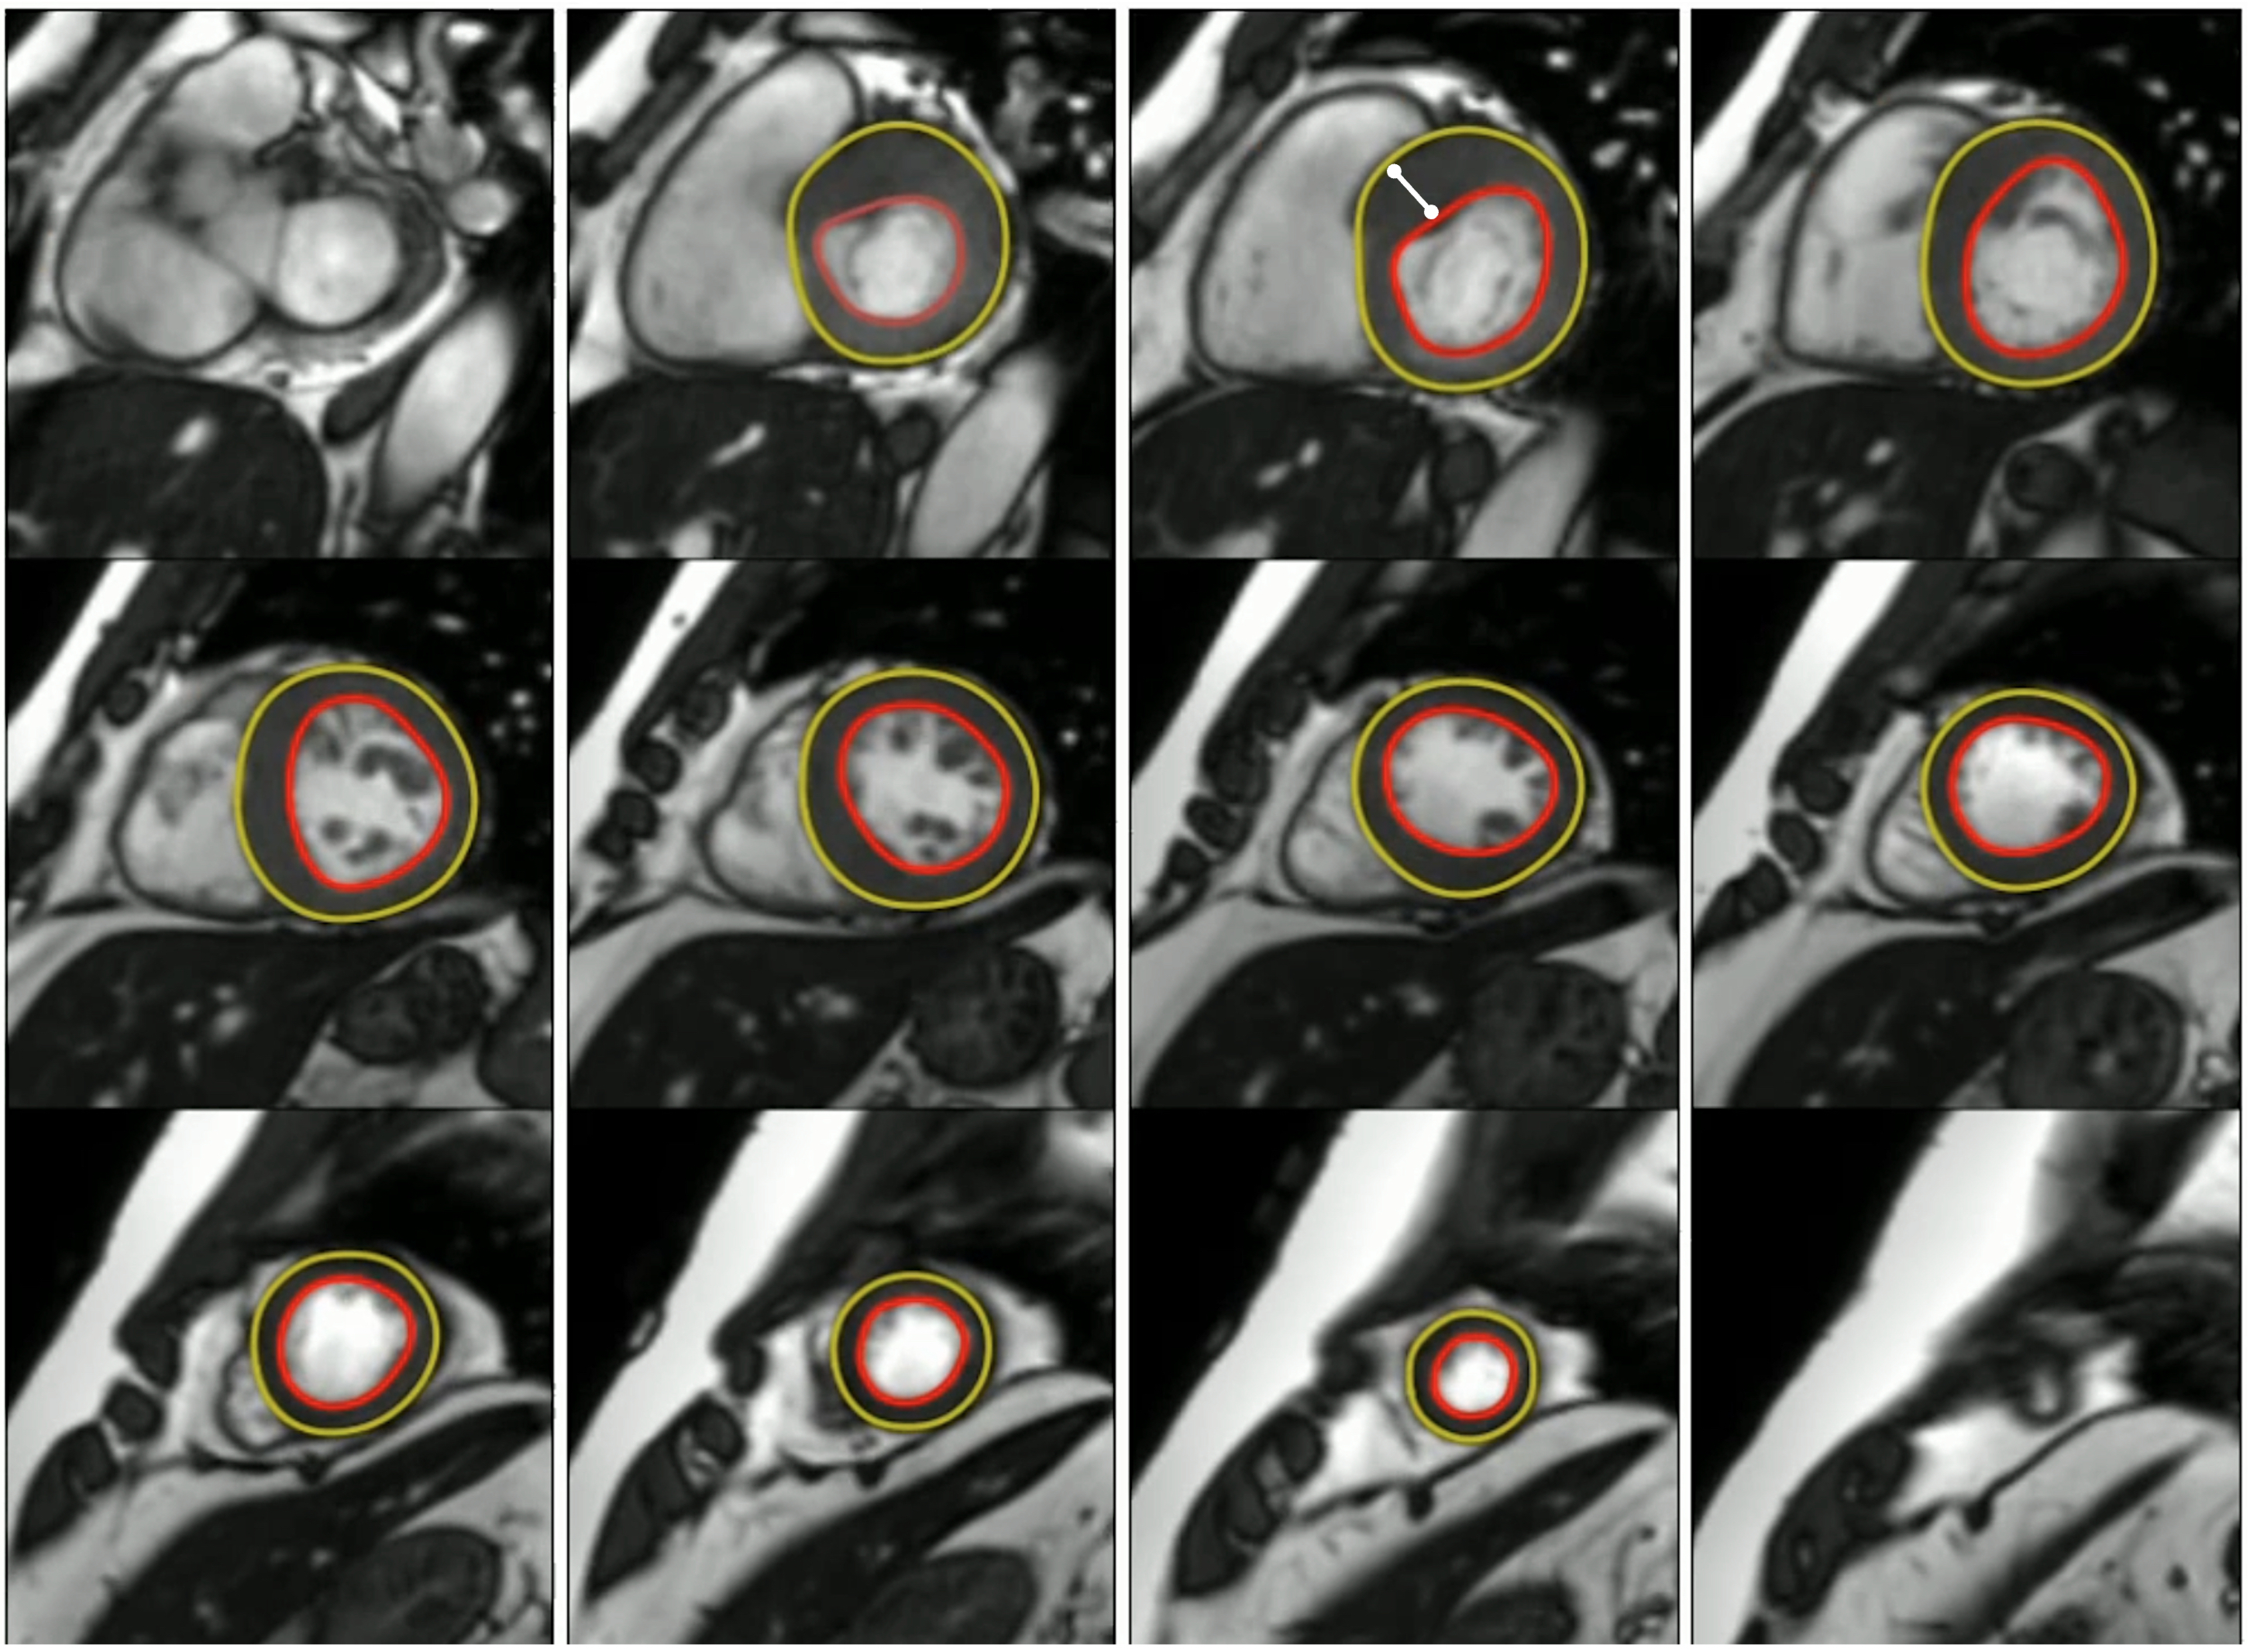

Artificial intelligence versus clinician maximum wall thickness measurement on cardiac MRI for mortality prediction

Maximum wall thickness (MWT) reflects left ventricular hypertrophy, which is associated with adverse prognosis in multiple diseases and at population level. In hypertrophic cardiomyopathy (HCM), MWT is a key marker in risk stratification and is commonly measured by expert clinician annotation. Artificial intelligence (AI) measurement of MWT has shown significantly higher precision than clinicians due to lower test-retest variability, but how this translates to clinical outcome is less understood.

We hypothesized that a deep-learning AI measurement of MWT obtained from cardiac MRI outperforms expert clinician annotation for the prediction of all-cause mortality.

AI measurement was performed on all CMR studies, and Cox proportional hazards models were fitted to compare the prognostic value of AI-derived MWT with those derived from clinician annotation used in clinical care.